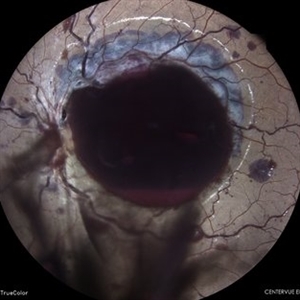

IOL Drop in a Case of Iridofundal Coloboma

Feb 7 2024 by Akansha Sharma

Color fundus photograph of a 43 year old male with IOL drop in a case of iridofundal coloboma.

Photographer: Dr. Akansha Sharma, Bharati Eye Hospital

Condition/keywords: chorioretinal coloboma, IOL drop